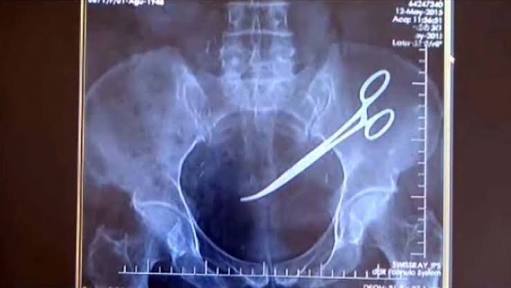

Doctors discovered the 15-centimetre (six-inch) scissors near his colon after a recent ultrasound.

He had a three-hour operation at the weekend to remove the scissors, according to Ngo Trung Thang, deputy head of general affairs at Gang Thep Thai Nguyen hospital, 80 kilometres (50 miles) north of Hanoi.